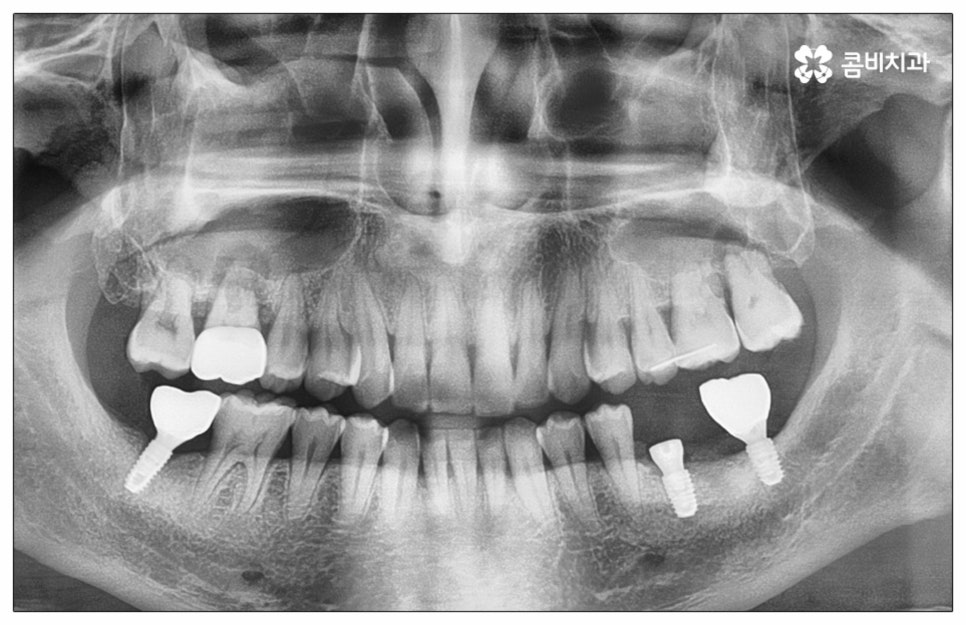

예전에는 이런 상황에서 틀니를 많이 이용하였으나 저작력 회복이 본래 자신의 치아 대비 20~30% 정도 밖에 되지 않고 잦은 탈락 위험 및 이물감, 잇몸을 눌러 장기적으로 잇몸뼈가 내려앉을 수 있다는 점 등 여러 가지 불편함이 있어 요즘은 임플란트 시술을 선호하시는 분들이 더 많아지고 있어요. 임플란트란 인체에 무해하며 잇몸뼈와 잘 결합하는 인공 치근을 잇몸뼈에 직접 식립하고 그 위로 기둥이 되는 중간 지대주와 치아 머리가 되는 크라운 보철물을 연결하여 인공 치아를 만들어 주는 시술을 말하는데, 자연 치아의 80% 정도 저작력 회복이 가능하기 때문에 식사를 할 때 음식을 크게 가리지 않아도 된다는 점 그리고 심미적으로 봤을 때 주변 치아와 자연스럽게 어우러진다는 점 때문에 각광을 받고 있습니다. 게다가 건강 보험 가입자이면서 만 65세 이상 부분 무치악 환자라면 평생 임플란트 2개까지 보험 적용을 받아 비용 부담을 줄일 수 있기 때문에 더욱 더 수요가 늘어나 이제는 치아 상실에 대체하는 대표적인 방법으로 임플란트 시술이 꼽히고 있는데요.

많이 대중화 되었다고 해도 임플란트 수술 자체가 술자의 숙련도에 크게 영향을 받는 복잡하고 고난도의 진료인 것은 틀림이 없기 때문에 담당 의료진이 해당 분야 임상 경험이 풍부한지, 뛰어난 기술력과 노하우를 가지고 있는지 꼼꼼하게 체크해 보실 필요가 있어요. 특히 노년층의 경우 당뇨, 고혈압 등 만성 질환을 앓고 있는 경우가 많아 혹시 상시 복용하고 있는 약이 있는지, 현재 환자 개개인의 상태는 어떤지, 사전 처치가 필요한 부분은 없는지 등등 수술 조건을 좀 더 까다롭게 평가한 후 환자분들과 이에 대해 충분히 상담하고 맞춤형 치료 계획을 세워 진행해야 하며 이를 위해 3D CT 와 같은 디지털 검진 장비를 통해 구강 내부 구조를 면밀하게 살피고 방대한 임상 데이터를 축적한 정품 임플란트 재료를 이용하여 연령이나 회복 정도를 살펴보면서 체력적 부담을 줄이는 방향으로 무리하지 않게 식립하는 것이 무엇보다 중요하다고 할 수 있습니다.

이때 추가 수술은 비급여 항목으로 건강보험임플란트 대상에서 제외되니 이에 대해서도 꼼꼼하게 살펴보시고 정밀 검진 후 담당 의료진과 자신의 상황에 대해서 충분하게 상담해 보시길 권유드리고 있습니다. 추가 수술의 대표적인 예로는 뼈이식 수술이 있는데요. 이것은 임플란트를 식립할 때 바탕이 되는 잇몸뼈의 높이나 폭, 밀도 등이 부족하다면 먼저 이를 보충해 주고 나서 임플란트를 심어주는 과정을 의미하며 같은 이유로 식립 성공률이나 장기적인 안정성을 높이기 위해 꼭 필요한 사전 처치, 즉 상악동 거상술 및 치주 질환 관련 수술 등을 먼저 해야 한다면 이 역시 추가 수술의 범주로 들어가니 자신의 상황에 대해서 상세하게 알아보실 필요가 있어요.